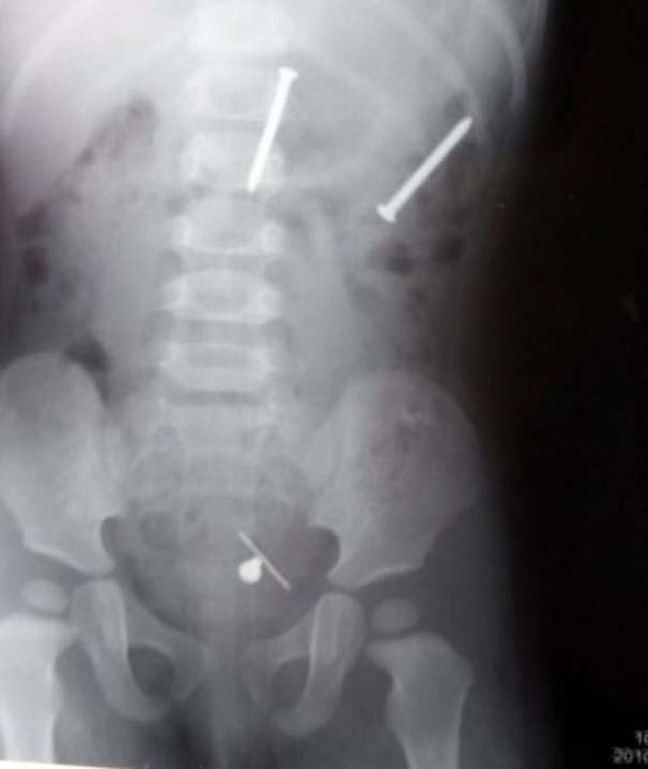

Ο,ΤΙ ΝΑ 'ΝΑΙ #φωτογραφίες Όταν μιλούν οι ακτινογραφίες! Αντικείμενα -και όχι μόνο- μέσα σε ανθρώπινα σώματα… 24·09·2013 13:33 16 σχόλια Δαχτυλίδι αρραβώνων Κλειδί Κουζινικά Χελι Μαγνητάκια Καρφιά 78 Κουτάλια και πιρούνια Φίδι